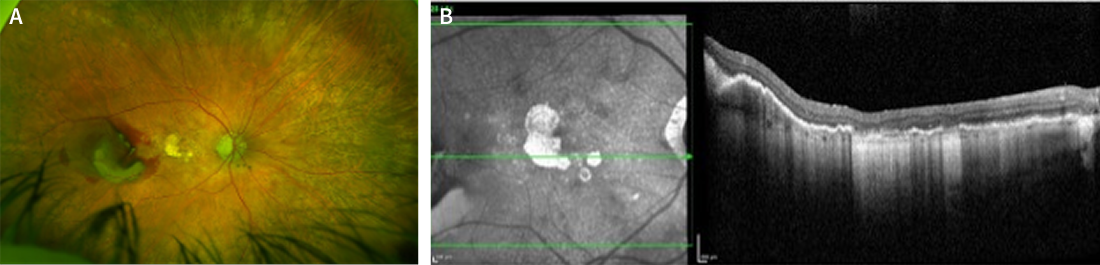

A 91-year-old man presented to our clinic in August 2022 with complaints of gradually decreasing vision in both eyes. He was previously diagnosed with geographic atrophy (GA) in both eyes. At the time of our examination, his medical history was positive for hypertension, chronic kidney disease, amyloidosis, dyslipidemia, and bladder and pancreas adenocarcinoma (both operated on and in complete remission/cure). Medications included apixaban (Eliquis, Bristol Myers Squibb), mirabegron (Betmiga), atorvastatin calcium (Lipitor, Upjohn), esomeprazole magnesium (Nexium, AstraZeneca), naltrexone, mirtazapine, and tafamidis. BCVA measured 6/9 OD and 6/60 OS. IOP was 10 mm Hg in each eye. Imaging captured at the time of the consultation demonstrated progression of the GA in both eyes compared to a prior visit in January 2019 (Figure 1). The patient was started on complement inhibition therapy (pegcetacoplan [Syfovre, Apellis]) in the left eye for three doses.

<p>Figure 1. OCT images of the right eye (A) and left eye (B) of the patient in August 2022 showing progression of GA lesions compared to January 2019 (C, right eye; D, left eye).</p>

Figure 1. OCT images of the right eye (A) and left eye (B) of the patient in August 2022 showing progression of GA lesions compared to January 2019 (C, right eye; D, left eye).